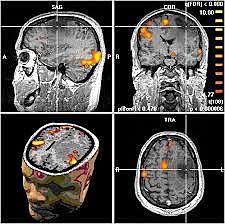

RESONANCIA MAGNETICA(RM) es una técnica que utiliza un campo magnético y ondas de radio para crear imágenes detalladas de los órganos y tejidos del cuerpo.

La mayoría de las máquinas de RM son grandes imanes con forma de tubo. Cuando te recuestas dentro de una máquina de RM, el campo magnético realinea temporalmente los átomos de hidrógeno en tu cuerpo. Las ondas de radio hacen que los átomos alineados produzcan señales muy débiles, que se usan para crear imágenes transversales de resonancia magnética,. La máquina de RM a también puede usarse para producir imágenes tridimensionales que pueden verse desde diferentes ángulos.

Peter Mansfield, físico inglés, descubrió el uso de gradientes de campo magnético producía señales que podrían ser analizadas para proveer la información espacial, incluyendo una descripción matemática de la transformación de una señal temporal a la representación espacial, introduciendo el concepto del espacio-K. Posteriormente siguió trabajando en la selección del corte y en 1976 propuso las secuencias EPI (eco-planar imaging), o como llenar el espacioK en forma rapidísima, en un solo disparo.

Publicaron imágenes de RM de la muñeca, R. Damadian logró reconstruir la imagen del tórax y P. Mansfield desarrolló las secuencias EPI. R. C. Hawkes y Moore et al en 1980 obtuvieron

las primeras imágenes de la cabeza y en 1981 se instaló el primer prototipo de tomógrafo por RM en el Hospital Hammersmith de Londres, dando inicio a los estudios pioneros de Graeme M. Vides, Ian R. Young en el departamento dirigido por el profesor Robert E Steiner.